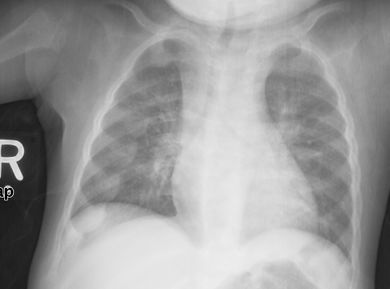

تميل الأشعة السينية أو التصوير الشعاعي لمريض متقدم يعاني من الكساح إلى الظهور بطريقة كلاسيكية: الأرجل المنحنية (الانحناء الخارجي لعظم الساق الطويلة) والصدر المشوه. تحدث التغييرات في الجمجمة أيضًا مما يؤدي إلى ظهور "رأس مربع" مميز يُعرف باسم "caput quadratum".[15] تستمر هذه التشوهات في سن البلوغ إذا لم يتم علاجها تشمل العواقب طويلة المدى التقوس الدائم أو تشوه العظام الطويلة والظهر المنحني[16]